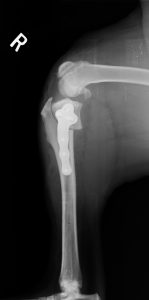

TPLO

アメリカで研究・開発されたシステムです。脛骨を特殊な器具で半円形に骨きりし、角度を変えることで前十字靭帯を必要としない関節角度を形成・維持します。専用のTPLOプレートを使用します。

36kg ラブラドール